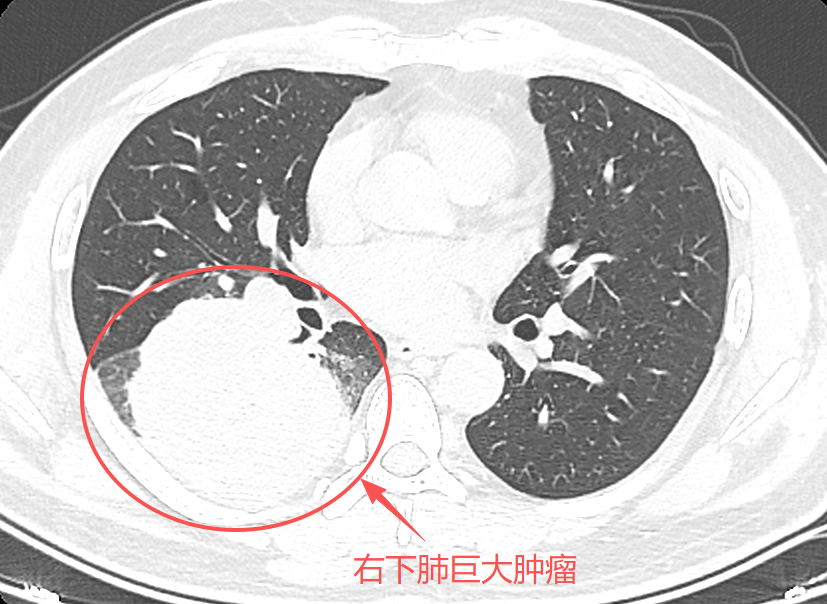

直至近期,持续性刺激性干咳的症状出现,随即来到我院检查,结果令人震惊——原本2公分的结节已疯长至近10公分,严重压迫支气管,引发剧烈咳嗽。同时穿刺活检证实为肺恶性肿瘤,虽暂未发现转移迹象,但如此巨大的肿瘤,无疑给治疗带来了极大挑战。

术后第四天复查,检查结果十分理想,患者顺利拔除引流管。复查胸部CT显示,患者肺复张良好,无胸腔积液、感染等并发症,近期将康复出院。